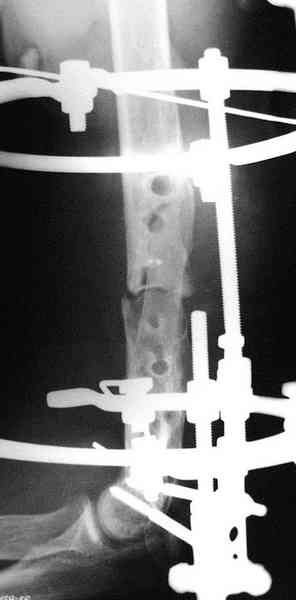

|

Уважаемый Алексей Минервин!

В подобном случае мы бы применили чрескостный остеосинтез. Пример - в приложении.

Всего наилучшего,

Л.Соломин